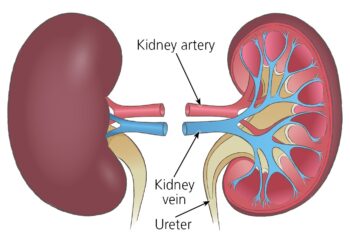

Read moreDetailsYadda Ake Kamuwa Da Ciwon Koda

Yadda Ake Kamuwa Da Ciwon Koda